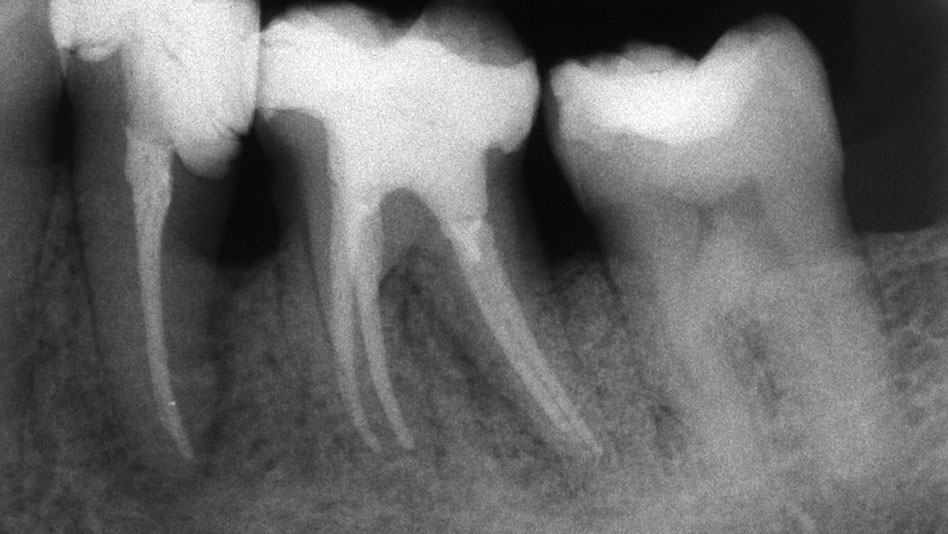

Periodontal disease is an extremely serious progressive condition which can lead to tooth loss if left untreated. Periodontal disease occurs when a bacterial infection in the gum pockets causes the bone and gum tissue to recede away from the teeth. The quality and quantity of bone and gum tissue is greatly reduced as the gum pockets continue to deepen. Fortunately, prompt diagnosis combined with effective regenerative procedures can halt the progression of the disease and save the teeth.

Dental implants and other restorative procedures depend on the jawbone being sufficiently strong and thick. When periodontal disease has taken hold, the jawbone may have become too thin to successfully support an implant. Natural bone regeneration (or bone grafting) is one of the best ways to promote growth and thicken the jawbone.

The aim of pocket reduction surgery is to reduce the depth of the gum pockets and make it much harder for bacteria to invade the gum tissue. Initially, the gum tissue is pulled back from the teeth and the subgingival area is thoroughly cleansed under local anesthesia. Extensive scraping may be required to fully remove the plaque, debris and tartar from below the gum line. An antimicrobial agent may then be applied to the affected area to kill any remaining bacteria, and the surgical site will be sutured closed. Pocket reduction surgery is very effective for halting tissue loss and promoting the natural healing of the gums.

The term scaling refers to the removal of plaque and calculus (tartar) from the supragingival region (above the gum line). This treatment is usually conducted in the course of a routine professional cleaning, and performed under local anesthetic. Root planing usually accompanies scaling and is performed in the subgingival region (below the gum line). Tartar and toxins are initially removed, and then the tooth root is smoothed down to promote good healing in the gum tissue. The planing of the tooth root provides a smooth area which prevents bacteria from recolonizing. If these procedures do not completely eradicate the infection, surgical measures may be required.